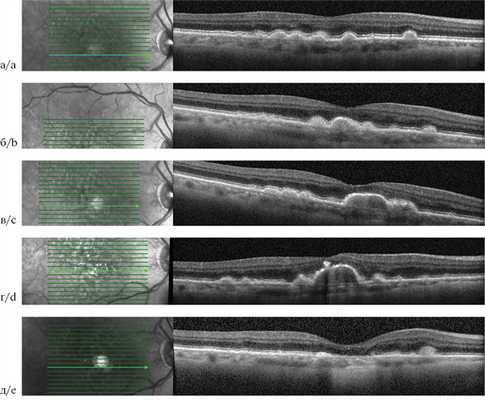

СТРОМАЛЬНАЯ КИСТА РАДУЖКИ: ОПТИЧЕСКАЯ КОГЕРЕНТНАЯ ТОМОГРАФИЯ И УЛЬТРАЗВУКОВАЯ БИОМИКРОСКОПИЯ ПЕРЕДНЕГО ОТРЕЗКА

Изображение стромальных кист радужки возможно получить либо с помощью относительно неинвазивной оптической когерентной томографии переднего отрезка, либо при помощи ультразвуковой биомикроскопии, требующей применения специальной ванночки для иммерсионной жидкости. Ультразвуковая биомикроскопия более информативна при выявлении патологических изменений, локализующихся за радужкой, тогда как оптическая когерентная томография переднего отрезка позволяет получить изображения радужки, передней камеры и роговицы высокого разрешения.

Стромальная киста радужки у ребенка. При оптической когерентной томографии переднего отрезка определяется кистозное образование. Стромальная киста радужки у взрослого. При гониоскопии определяется киста, распространяющаяся на структуры угла передней камеры. При ультразвуковой биомикроскопии определяется сдавливающая радужку киста, поражение цилиарного тела отсутствует. При оптической когерентной томографии определяется сдавливающая радужку киста. Современные системы не позволяют визуализировать глубжележащие структуры.